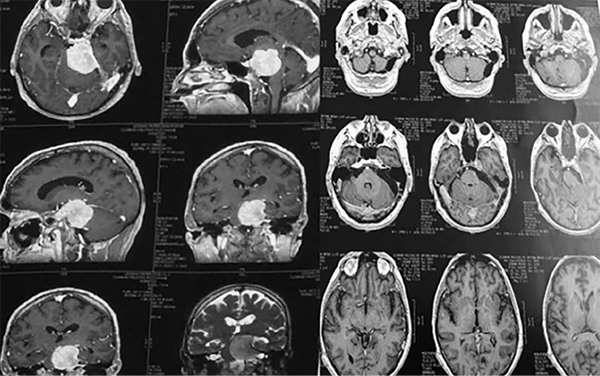

Por definición, los meningiomas petroclivales tienen su origen medial a los pares craneales V, VII, VIII, IX, X y XI, y pueden alcanzar el tentorio.1,3,5,6 A menudo se extienden hacia la fosa media, el seno cavernoso y la cisterna prepontina (Figura 1). Pueden descender al agujero magno, pudiendo invadir la piamadre y causar compresión del tronco encefálico. En los casos en que hay edema del tronco encefálico (hipodensidad en la tomografía o hiperseñal enT2 en la resonancia magnética) o una forma dentada e irregular del tumor sobre el tejido cerebral, la extracción total es muy difícil o imposible sin causar déficits neurológicos3-5(Figura 2). Los meningiomas del clivus inferior (foramen magno), petrosos, tentoriales y del ala esfenoidal pueden alcanzar estas áreas, pero no se consideran de origen petroclival.6

Figura 1: Resonancia magnética axial en T1 con gadolinio. Meningioma petroclival (izquierda), meningioma esfenopetroclival (centro), meningioma petroso (derecha).

Figura 2: Resonancia magnética que muestra la forma dentada del borde del tumor (izquierda) y tomografía que muestra edema del tronco encefálico. Éstos son hallazgos que indican la ausencia de un buen plan de disección entre el tumor y el tronco encefálico.